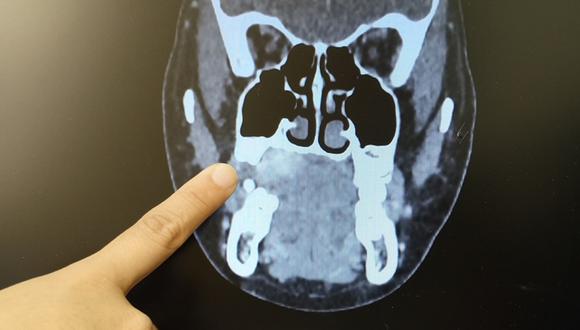

Así, con la referencia médica, en enero pasado llegó al INSN Breña, donde le realizaron diferentes exámenes, entre ellos una tomografía. La Dra. Isabel Pisfil Valenzuela le diagnosticó a la menor un tumor mucoepidermoide de reborde alveolar (encía) lado derecho.

“Este es un tipo de cáncer que se origina en las glándulas salivales menores que tienen una distribución a nivel de todo el tracto aerodigestivo. Es decir están en la boca, en la garganta y pueden ubicarse hasta la parte de la laringe”, explicó la especialista.

El pasado 21 de enero, la menor fue operada en el INSN Breña y se le extrajo un tumor de 2.5 x 2.00 cm. También le retiraron cuatro piezas dentales para llegar a la zona del tumor.

La intervención quirúrgica duró tres horas. Este tumor amenazaba con extenderse a los ganglios del cuello y de ahí podría haber avanzado hasta el pulmón, informó la especialista en Cabeza y Cuello.